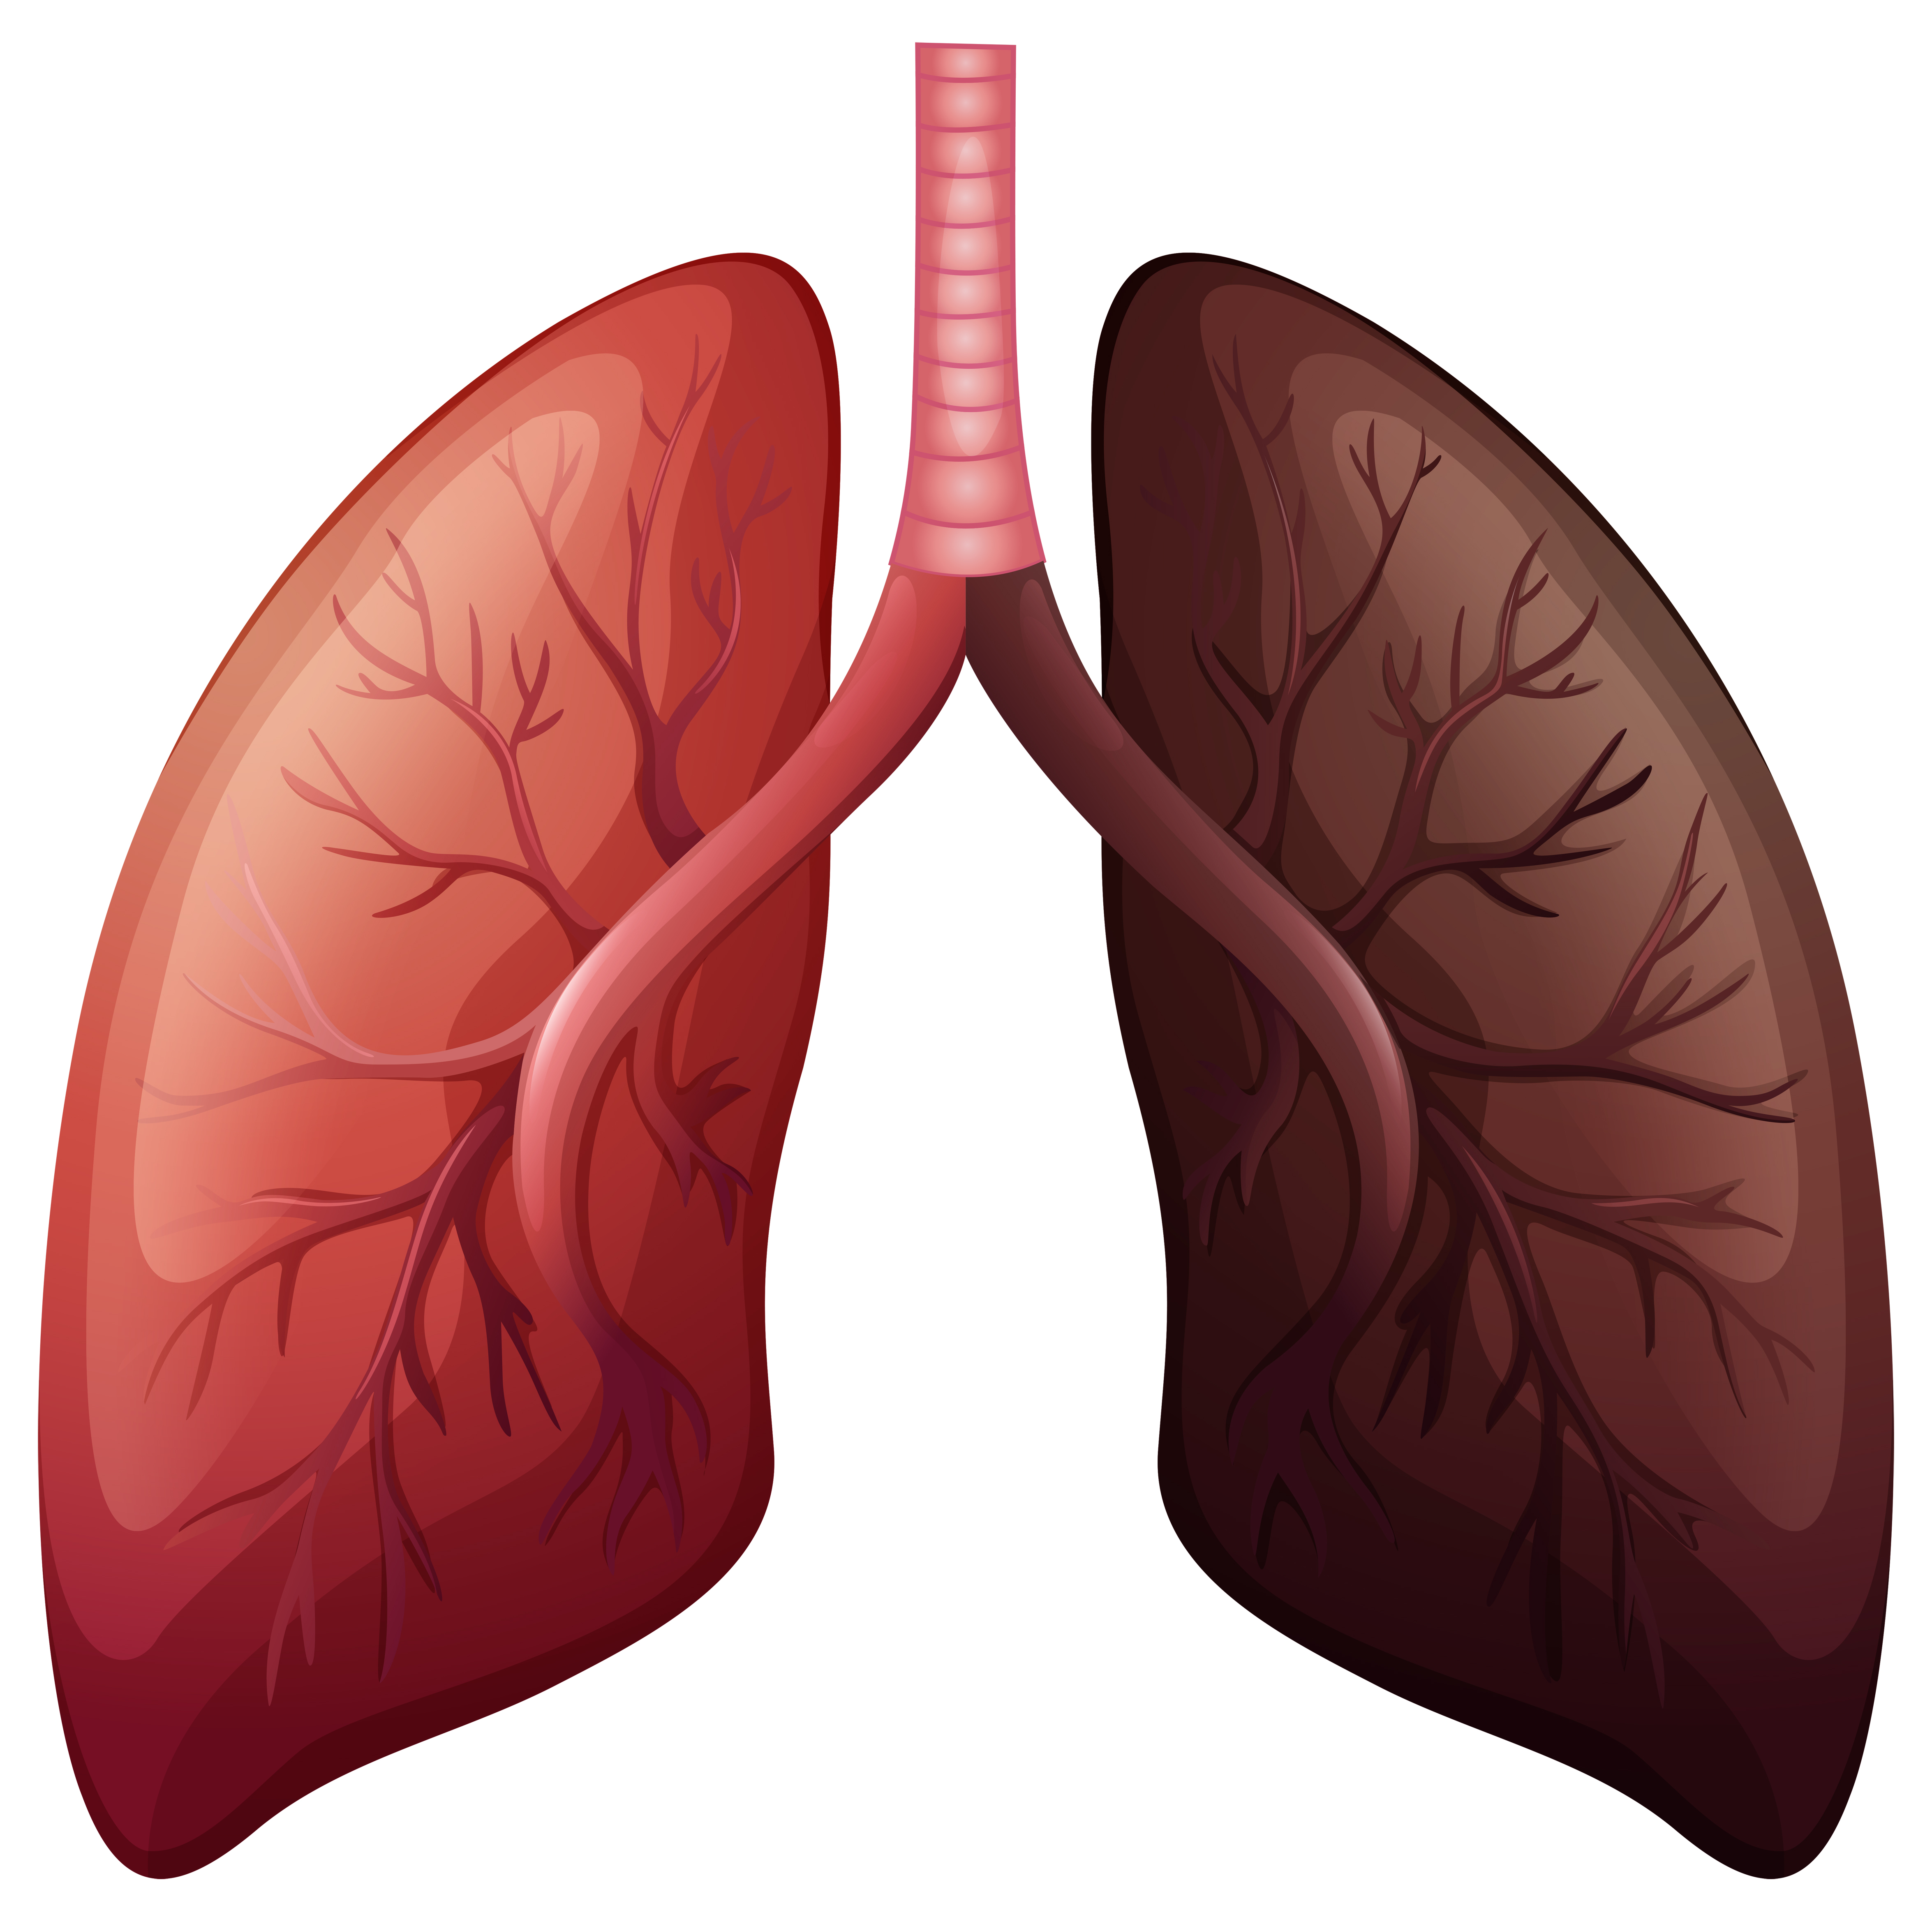

Здоровые Легкие Картинки

Здоровые Легкие Картинки 117 фото